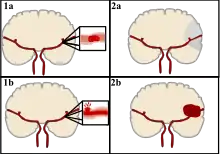

Classification

Stroke can be classified into two major categories: ischemic and hemorrhagic.[19] Ischemic stroke is caused by interruption of the blood supply to the brain, while hemorrhagic stroke results from the rupture of a blood vessel or an abnormal vascular structure. About 87% of stroke is ischemic, with the rest being hemorrhagic. Bleeding can develop inside areas of ischemia, a condition known as "hemorrhagic transformation." It is unknown how many cases of hemorrhagic stroke actually start as ischemic stroke.[2]

There are two main types of hemorrhagic stroke:[29][30]

- Intracerebral hemorrhage, which is bleeding within the brain itself (when an artery in the brain bursts, flooding the surrounding tissue with blood), due to either intraparenchymal hemorrhage (bleeding within the brain tissue) or intraventricular hemorrhage (bleeding within the brain's ventricular system).

- Subarachnoid hemorrhage, which is bleeding that occurs outside of the brain tissue but still within the skull, and precisely between the arachnoid mater and pia mater (the delicate innermost layer of the three layers of the meninges that surround the brain).